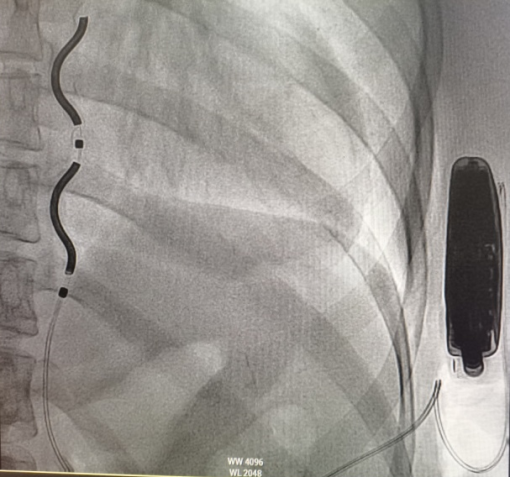

在麻醉科韩宝庆副主任医师实施全麻下,手术由该院心血管内科八病房韩颖主任医师牵头,高宇囡主任医师、张雪岩主治医师等团队成员默契配合,严格遵循无菌操作规范与精准解剖定位原则。术中,通过反复X线引导精准规划植入路径,将电极妥善植入胸骨后,脉冲发生器植入左侧胸壁皮下囊袋内,整个过程历时2小时余,顺利完成电极测试与设备调试,诱颤后除颤成功,手术取得圆满成功。术后患者生命体征平稳,胸闷、心悸等症状明显缓解,目前已顺利康复出院。

EV-ICD植入术后影像